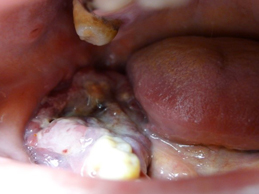

В настоящее время выявляемость рака полости рта среди нашего населения происходит на третей, четвертой стадии с локализацией на языке, подъязычной области, нижней губе и десне (фото 2, 3, 4, 5, 6)

Фото 2

Фото 3

Фото 4

Фото 5

Фото 6